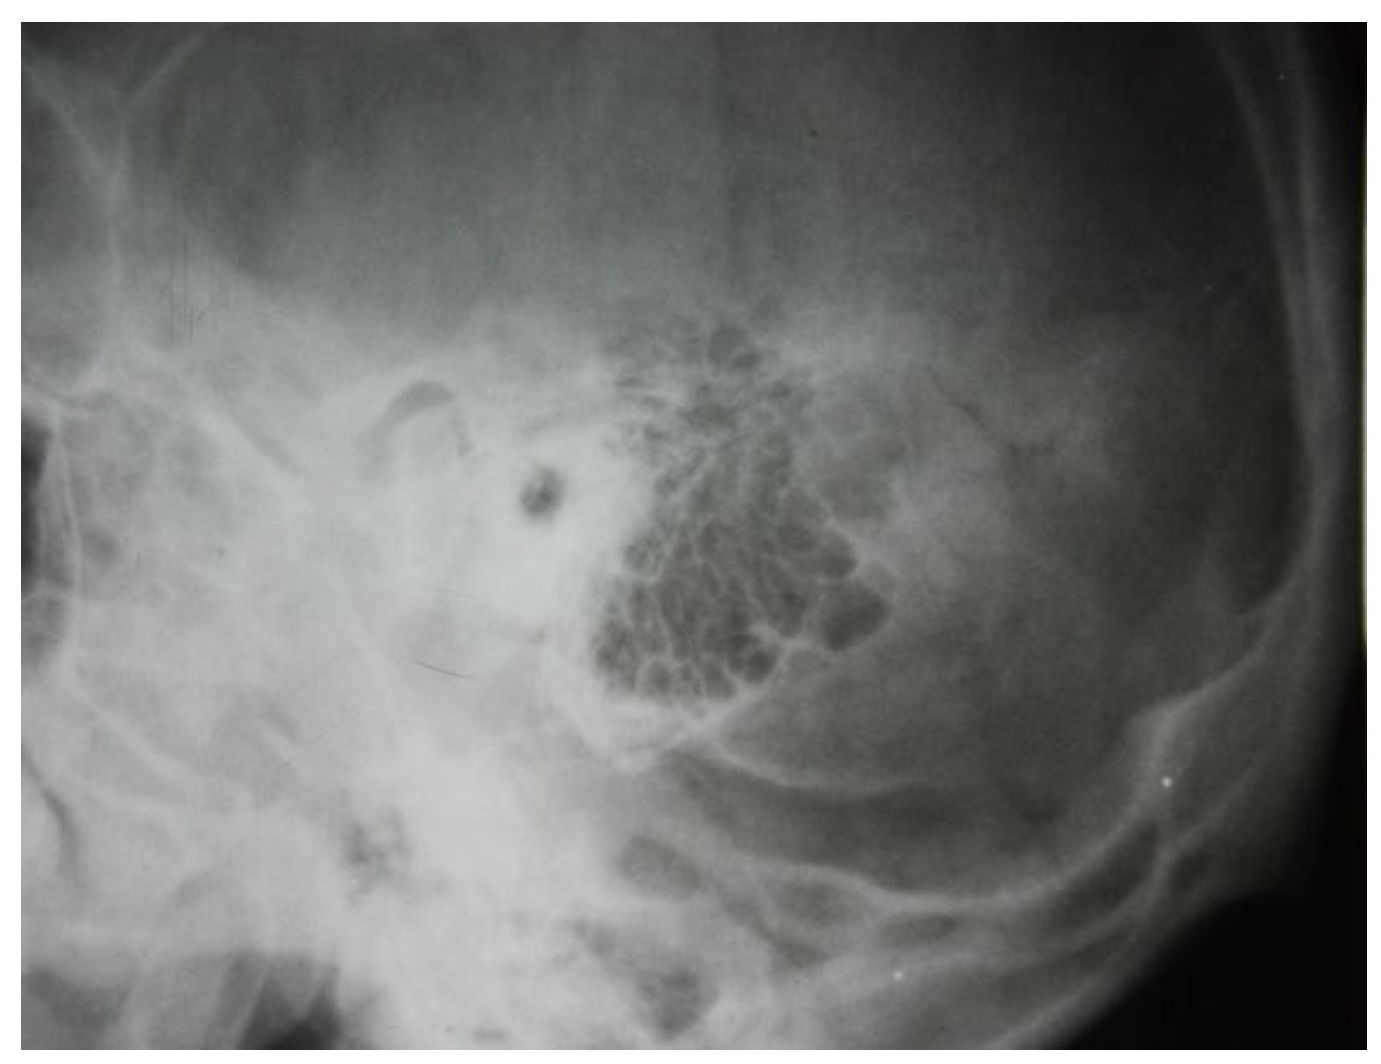

3.1.1. Conventional Radiology